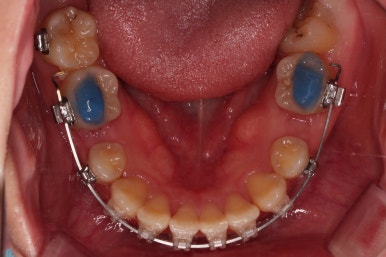

우선 장치를 부착해요.

환자분이 선택하신 장치는 엠파워 클리어라고 하는 자가결찰 세라믹 장치에요.

흔히들 클리피씨라고 많이 알고 계신 장치도 자가결찰 세라믹 장치의 한 종류에요.

제조사가 일본(클리피)이냐 미국(엠파워)이냐의 차이일 뿐이죠.

장치 부착 후에 순차적으로 4개의 치아를 발치해주고요.

치아를 뽑은 위치, 당겨야 할 정도가 달라 미니스크류를 몇 개 사용했어요.

미니스크류는 앞뒤조절, 높낮이 조절, 각도 조절, 안밖의 위치조절 등 난이도 높은 치료를 가능하게 해준답니다.